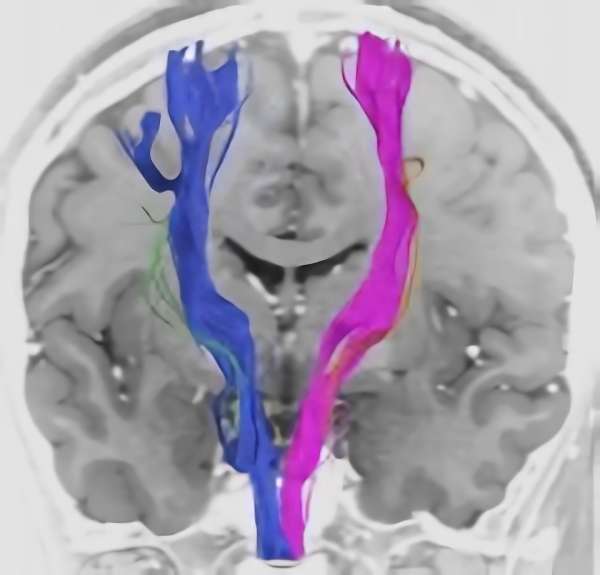

脳血管撮影

手術前

手術後

手術中

モニタリング

手術写真

手術の結果